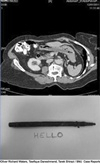

데일리메일의 보도에 따르면 최근 신원이 공개되지 않은 76살의 이 여성은 여성은 25년 전 펜을 이용해 목 깊숙한 곳을 들여다보는 중 실수로 펜을 삼켰지만 당시 의료기술이 발달되지 않아 펜을 발견할 수 없었다고 한다. 하지만 최근 소화 불량 복통 체중 감소 등으로 의사를 찾았다가 CT 촬영 등을 통해 여성의 위장에서 펜을 발견했고 곧장 수술을 통해 펜을 꺼냈다. 그녀의 위장에서 꺼낸 펜은 지금도 잉크가 있으며 종이에 글씨를 쓸 수도 있는 것으로 전해졌다.